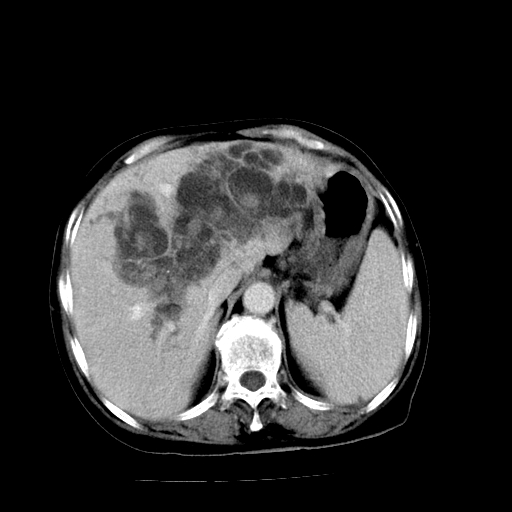

以下是引用随光逐影在2009-4-7 8:21:00的发言:[br]肝内外胆管多发性结石并肝内外胆管扩张;胆系感染。